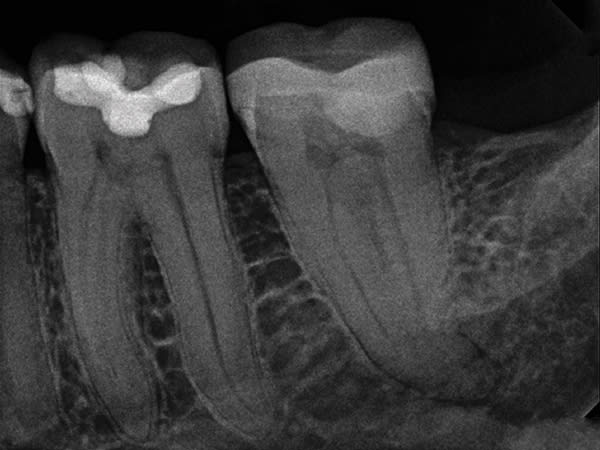

A C-shaped molar root canal can cause even seasoned clinicians to question whether to perform treatment in a one- or two-visit procedure. Tortuous anatomy and unusual root complexities make it difficult to clear all the tissue from the root canal system. Clinicians often opt for sonic or ultrasonic irrigation and a two-visit procedure to assure a positive clinical outcome. In this case, GentleWave® Procedure Multisonic Ultracleaning® technology (Sonendo, sonendo.com) was used to treat irreversible pulpitis in a C-shaped lower second molar, which is often difficult to address. After administration of anesthesia, and with the use of a dental microscope (Leica M320, Leica Microsystems, leica-microsystems.com), conservative straight line access was achieved, and three canals were located, measured, and instrumented. The GentleWave Platform was then built onto the tooth, the Procedure Instrument attached to the GentleWave Console, and the GentleWave Technology finished the procedure. Eight minutes later, the platform was removed, the canals dried, and the canal system filled. Upon completion of the GentleWave Procedure and warm vertical obturation the results were astonishing as evidenced in the final radiograph.

Endodontic challenges such as a C-shaped molar root canal can be treated successfully in one visit with minimal instrumentation and the GentleWave Procedure.

Closed-loop Multisonic Ultra-cleaning technology reaches deep into lateral canals and microscopic tubules to remove tissue, debris, biofilm, and bacteria. It also helps preserve the integrity of the tooth by leaving dentin intact.

With advanced fluid management, the self-contained GentleWave System delivers the precise concentration of procedure fluids, resulting in the simultaneous ultracleaning of each canal from crown to apex.